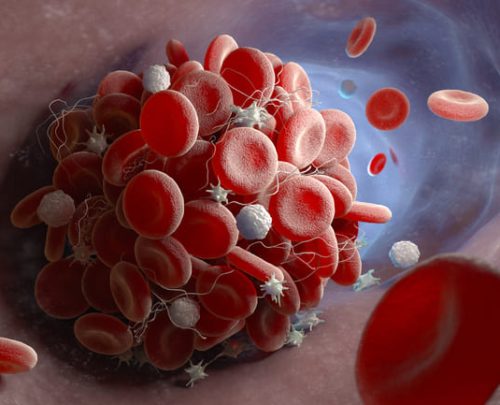

TROMBOSE VENOSA PROFUNDA

Diagnóstico e tratamento de coágulos sanguíneos nas veias.